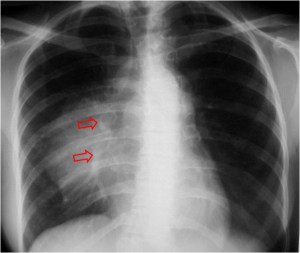

SIGNO DEL TUMOR FANTASMA O TUMOR EVANESCENTE

Signo que describe al derrame pleural atrapado en la cisura menor, especialmente en pacientes con insuficiencia cardiaca. El derrame loculado en la proyección posteroanterior se ve como una lesión nodular o masa que simula un tumor sólido (imagen superior). Sin embargo, la evolución rápida hacia la desaparición de esta lesión sugiere que se trata de derrame.

Vemos en las imágenes un tumor fantasma que desaparece en el control realizado cinco días más tarde.

En la primera imagen, la presencia de derrame pleural asociado y el engrosamiento del resto de la cisura menor, visible como una línea superpuesta al tumor fantasma, sugieren el diagnóstico.